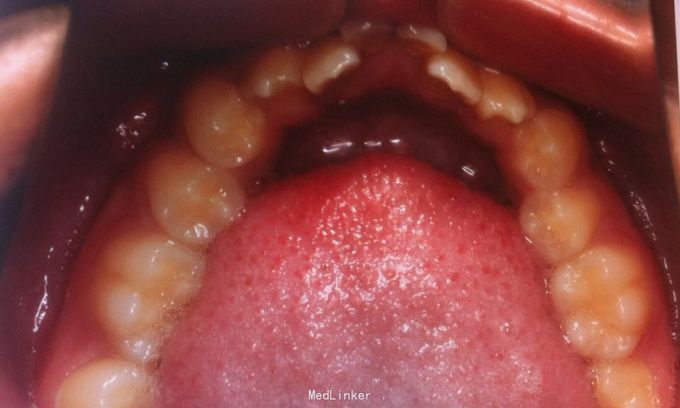

恒牙期 25正锁合 磨牙中性关系 前牙一度深覆盖深覆合 牙列拥挤 张口型异常

安氏一类 不拔牙矫治,直丝弓矫治器,排齐整平上下牙列,治疗后前牙覆合覆盖正常,磨牙中性关系,维持现有面型